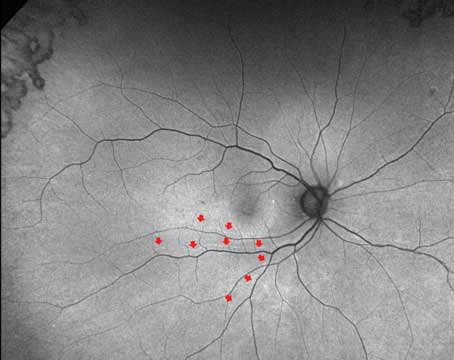

How multimodal imaging raises the bar for RRD repair

The potential of imaging biomarkers are emerging as useful outcome measures for future trials in rhegmatogenous retinal detachment.